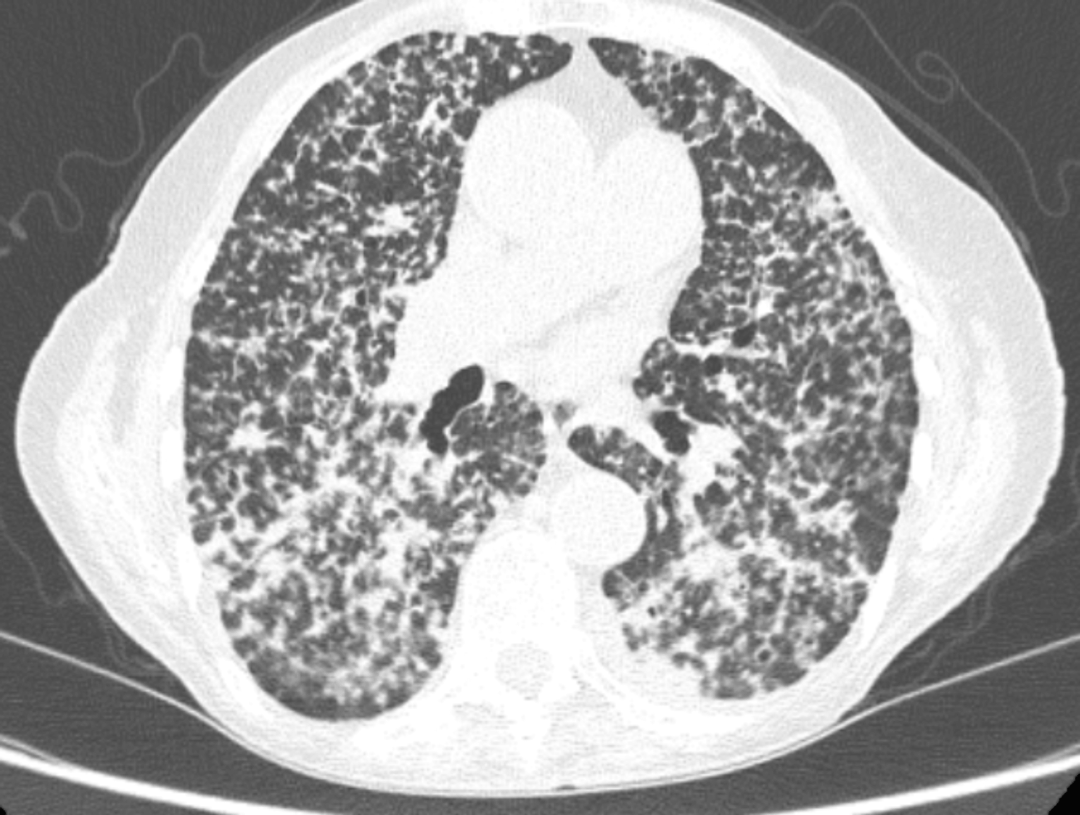

分期检查:胸部CT分期示双侧肺内多叶受累,诊断为T4N0M1a期肺腺癌(图4)。

图4 再次胸部 CT